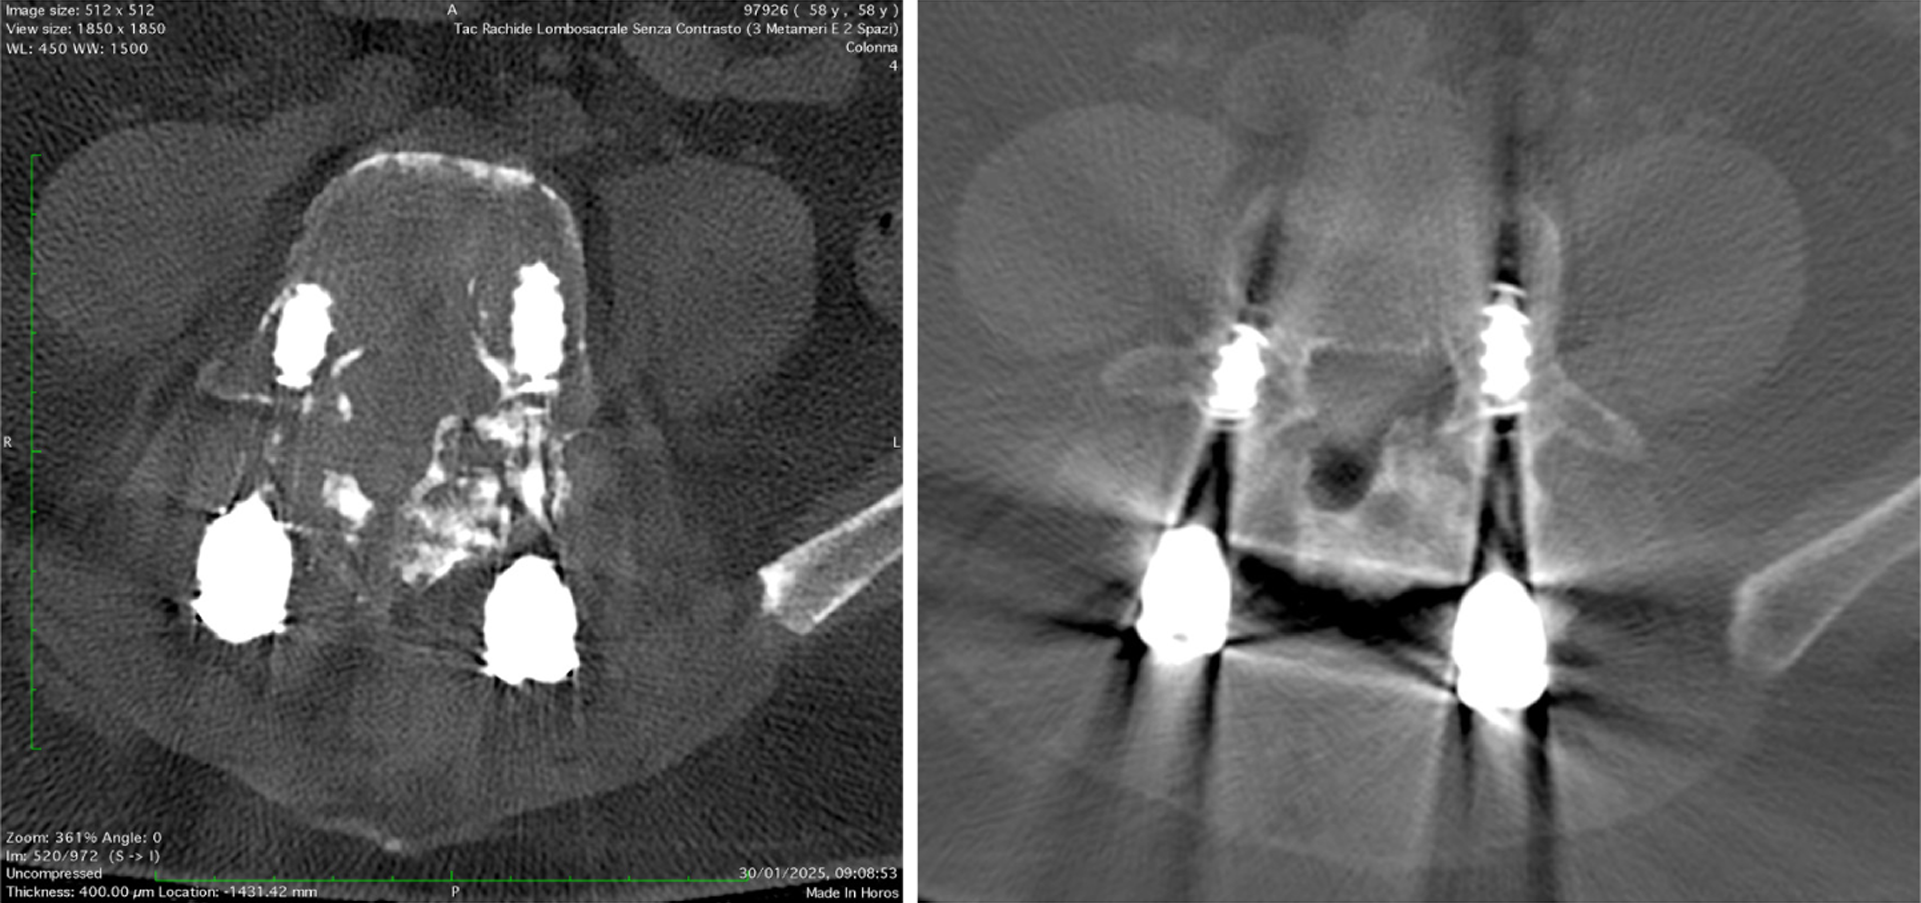

Figure 6 Axial high-resolution computed tomography image of the right temporal bone.

On the photon-counting computed tomography image on the right is clearly evident a focus of otospongiosis that cannot be clearly identified on the traditional computed tomography image on the left. Visualized in the form of a hypodense demineralized otosclerotic plaque is noted in the fissula ante fenestram.